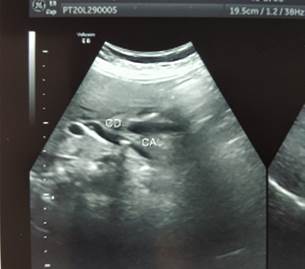

Given the CBD stones, an MRCP was done. It showed a contracted gall bladder with small intra-luminal filling defects. Intrahepatic biliary radicals were not dilated, but the right and left hepatic ducts were prominent. CBD was dilated with a maximum diameter of 8.4mm. Intra-luminal filling defects were seen in mid-CBD, the largest one being 8.1 mm.

Figure 2: MRCP showing dilated CBD and filling defects

The CBD had a doubtful filling defect. We proceeded with a wire-guided sphincterotomy and balloon sweeping. Balloon sweeping yielded sludge. A 10 Fr 5 cm stent was placed inside the CBD at the end of the procedure (Figure 2).